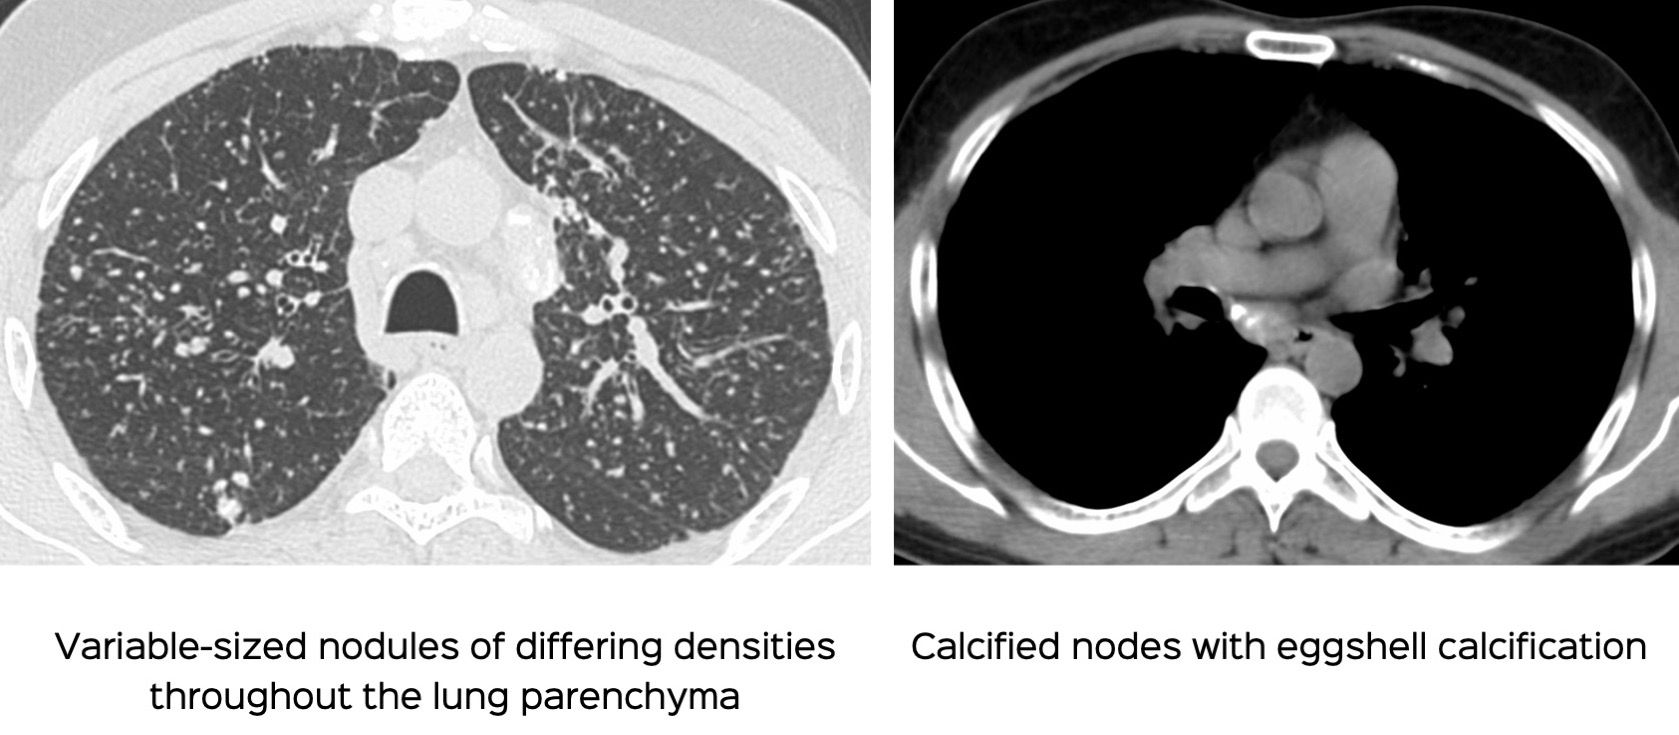

Case 88: Flour Mill Worker Disease

This combination of variable sized lung nodules and eggshell calcification is characteristic.

A 48-years old flour mill worker presented with gradually progressive breathlessness.

- Silicosis